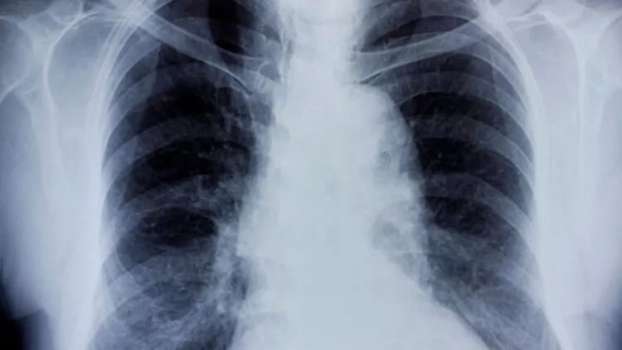

Bronşit Nedir?

Bronşit, akciğerlerinize hava taşıyan bronşların iltihaplanmasına verilen isimdir. Bronşit, akut veya kronik olabilen bir hastalıktır. Genellikle soğuk algınlığı veya başka bir solunum yolu enfeksiyonuyla birlikte akut bronşit gelişebilmektedir. Kronik bronşit ise daha ciddi bir durumdur ve genellikle sigara içmeye bağlı olarak bronşiyal tüplerin astarının sürekli olarak tahriş olması veya iltihaplanmasıyla ortaya çıkmaktadır.